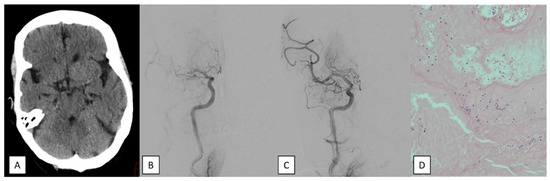

Percutaneous Transluminal Angioplasty and Stenting for Symptomatic Intracranial Stenosis After SAMMPRIS: Patient Selection and Clinical Outcomes

by Leonhard Mann, Patrick Felix Samp, Jan Hendrik Schaefer, Elke Hattingen, Joachim Berkefeld, Dimah Hasan and Fee C. Keil

Background/Objectives: After the negative results of the SAMMPRIS trial, the indication for endovascular treatment of atherosclerotic intracranial artery stenosis (ICAS) was widely restricted. It was the aim of our study to report whether intracranial arterial percutaneous transluminal angioplasty and stenting (PTAS) as ultima [...] Read more.

Background/Objectives: After the negative results of the SAMMPRIS trial, the indication for endovascular treatment of atherosclerotic intracranial artery stenosis (ICAS) was widely restricted. It was the aim of our study to report whether intracranial arterial percutaneous transluminal angioplasty and stenting (PTAS) as ultima ratio therapy is still effective and safe enough. Methods: Between February 2011 and June 2019, 63 consecutive patients with and without emergent large vessel occlusion (ELVO) who received PTAS for symptomatic ICAS in the anterior or vertebrobasilar circulation were included in our study. Results: A total of 32 patients had ELVO. In the remaining 31 patients, a known ICAS was treated with PTAS either because of recurrent stroke despite aggressive medical therapy with dual antiplatelet inhibition (n = 24) or due to progressive hemodynamic ischemia (n = 7). Stenting was successful in all 63 cases. Successful reperfusion was achieved in 94% of ELVO patients. Complications with new neurologic deficits, including dissection, subarachnoid hemorrhage, intracerebral hemorrhage (PH2), and stent thrombosis, were seen in five ELVO patients (16%). At discharge, neurological status improved in 16 patients (50%) and deteriorated in 7 patients (22%). In-hospital mortality happened in 5 of 32 ELVO cases (16%), and all of them had lesions in the vertebrobasilar circulation. Regarding non-ELVO cases, two patients (6%) developed new neurologic deficits due to perforator strokes. There was no in-hospital mortality in this group. Conclusions: Even in unfavorable situations with acute atherothrombotic occlusions or recurrent strokes under aggressive medical therapy of known ICAS, PTAS remains a treatment option with reasonable effectiveness. This should be balanced against other treatment options, taking into account the complication rate, which is not negligible. Full article

Show Figures

Figure 1